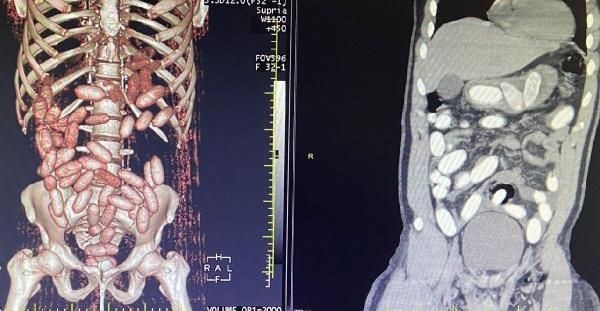

Gümrük Muhafaza ekiplerince savcılık talimatı doğrultusunda detaylı bilgisayar tomografi çekilmesi için sağlık kuruluşuna götürülen 6 yolcunun yapılan tarama ve muayenelerinde 761 adet ve toplam ağırlığı 10 kilo 420 gram kokain tespit edildi.

Yolcuda, 'yutucu' tespit cihazı ve ardından sağlık kuruluşunda yapılan muayene sonucu 48 adet kapsül ve toplam ağırlığı 760 gram kokain ele geçirildi.